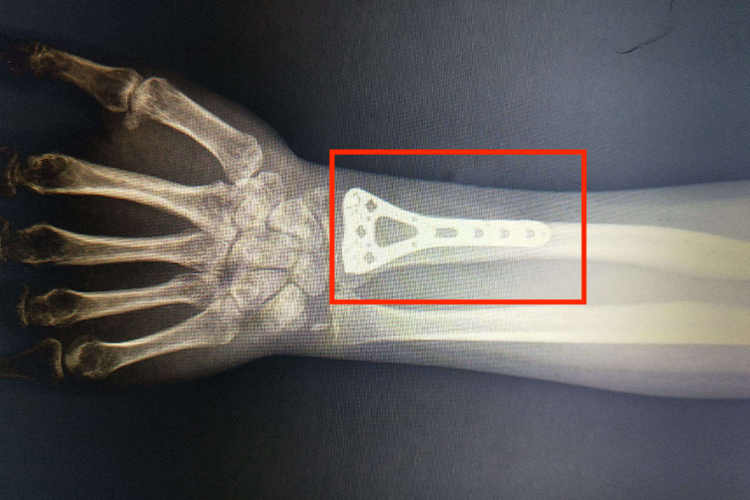

手腕桡骨骨折后,如果检查发现是开放骨折、多段骨折,以及复位失败、固定困难时,应切开进行复位,使用钢板、加压钢板等物质进行内固定。手术后,通过影像学可观察到明显的钢板内置形态。